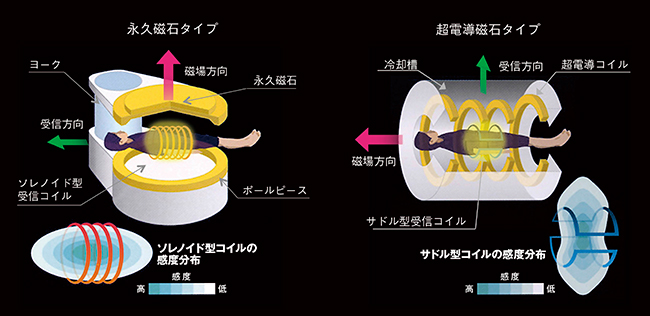

1.磁場方向の「違い」(表1,図2)

磁場の方向の違いは,受信コイルによる信号収集効率にも影響を与えます。受信コイルは静磁場方向に対して垂直に設置する必要がありますが,垂直磁場タイプではソレノイド型コイル,水平磁場ではサドル型やサーフェス型を複数組み合わせたフェイズドアレイコイルを用います。ソレノイド型は同じ大きさのサドル型に比べておよそ倍のSNRが得られ,コイルで囲んだ中心領域の感度が高くなりますが,被検者や目的部位の大きさに合わせたサイズのコイル選択が重要となります。

水平磁場ではフェイズドアレイコイルを用い,コイル表面の感度が一番高くなります。そのため,水平磁場方式では,中心感度を持ち上げる感度補正が必要となり,永久磁石タイプでは必要のない感度マップの撮像を行います。また,複数のコイルを組み合わせて使用できるため,パラレルイメージングが可能となります。

図2 磁場方向・コイル方式の違い